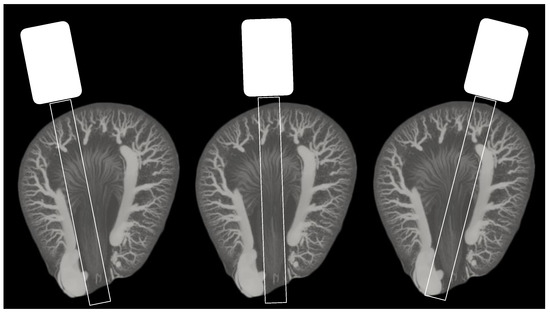

Figure 4. Illustration of three different ultrasound probe positions (coronal slice) on an axial slice maximum intensity projection (50 slices) from an ex vivo µCT of a Sprague Dawley rat kidney filled with intravascular Microfil (from a separate study). The image in the middle demonstrates the optimal position for visualization of inner and outer medulla, as the two other positions can include more of the surrounding tissue, larger vessels, and vasa recta going in the elevational direction.

The old rats showed a denser vasculature in OZR in CO veins/venules and OM venules. The density in CO veins/venules was increased in OZR despite a comparable number of tracks (1974 in OZR and 2128 in LZR). A comparable number of tracks was also present in OM venules: 2222 in OZR and 2074 in LZR. A decrease in old IM arteriole density (1705 in LZR and only 1192 in OZR) was seen despite a similar number of detected MBs. In Figure 4, the possible effect of probe positioning on the medullary vascular density is illustrated and this effect is discussed in the next section.

The vascular density difference varied in all renal regions in the young and old rats. For example, a large difference was found in the cortical arteries/arterioles and veins/venules with a coefficient of −0.68 and −0.57, respectively (Table 3). The young rats were used as a baseline prior to any expected structural alterations, and the substantial difference in density between the OZRs and LZRs was not anticipated. However, the number of detected MBs, and thereby the number of generated tracks, were very different between the young OZRs and LZRs (Table 2). In the 20-week-old group, an increased vascular density was found in the OZRs compared with the age-matched controls in the cortical veins/venules and OM venules corresponding to the observations found using ex vivo µCT [32,33]. However, in this group, the number of tracks also varied in other regions due to the variation in MB detections. The complexity of MB-based super-resolution imaging and the derived vascular representations makes in vivo vessel quantification challenging. In this study, the measured density difference was inevitable, since the density metric is affected by the number of generated tracks. It is important to have a similar number of MBs per frame in all animals and the number of MBs per frame needs to be suitable for the area or organ of interest in order to generate reliable and comparable tracks. However, it is difficult to control number of MBs in vivo, which is a known problem in SR ultrasound imaging [34,35]. To accommodate this challenge, implementation of an MB counter could increase the probability of making the scans homogeneous and reproducible [36]. Alternatively, a feedback system indicating the number of MBs in the contrast-enhancing display could allow more precise adjustments of the MB infusion rate. In addition, the metrics may also be affected by the 2D nature of the SR ultrasound imaging, as slight differences in scan plane can potentially change the quantitative outcome [37]. For example, for the IM, which is thin in the elevational direction, a difference in probe position may affect the number of vasa recta included in the scan plane (Figure 4).